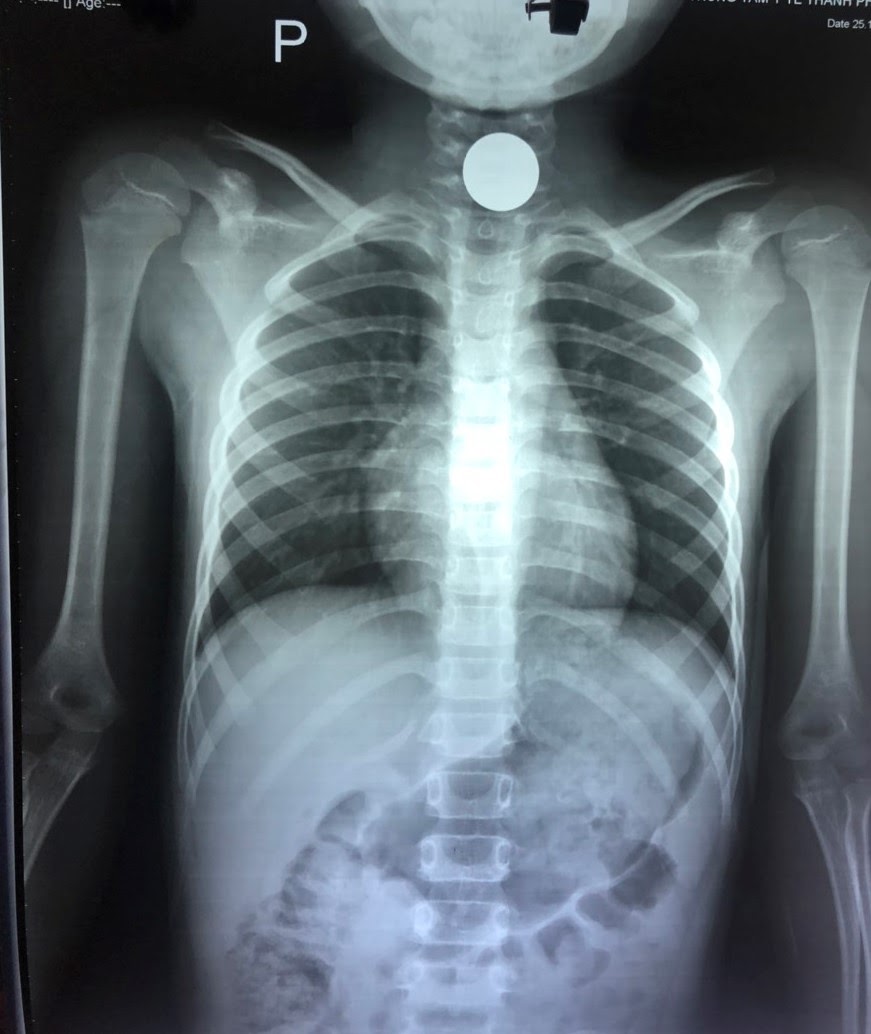

Theo lời kể gia đình, vào 12 giờ 30 phút cùng ngày bệnh nhi tự nuốt vật lạ là một đồng xu. Kết quả chụp X-quang cho thấy hình ảnh dị vật nằm ở vị trí thực quản vùng cổ.

Sau khi hội chẩn chuyên khoa với kíp nội soi, các bác sĩ chỉ định nội soi tiêu hóa cấp cứu gắp dị vật cho bệnh nhi. Kết quả nội soi ghi nhận dị vật là một đồng xu ở vị trí thực quản vùng cổ. Với tính chất tròn của dị vật, nếu không loại bỏ kịp thời có thể gây chèn ép đường thở, nguy hiểm đến tính mạng của người bệnh. Các bác sĩ đã tiến hành dùng kìm gắp dị vật để gắp đồng xu ra ngoài, sau đó soi kiểm tra lại tình trạng thực quản ổn định, không còn dị vật nào khác.